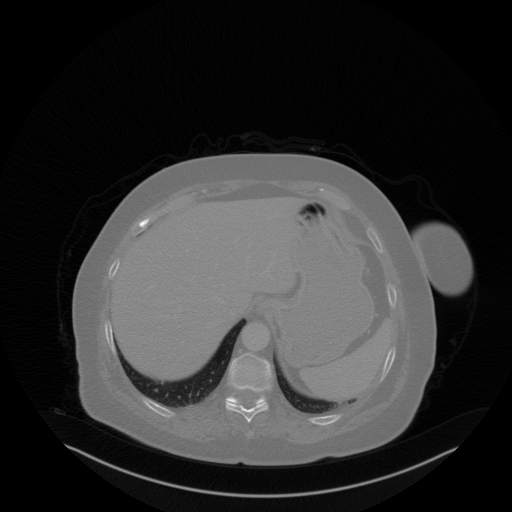

Reconstructed NATIVE CT scan (cycle consistency)

No window - Raw intensity values

Lung window (WL -600, WW 1500 β†’ Low βˆ’1350, High +150)

Mediastinum window (WL 40, WW 400 β†’ Low βˆ’160, High +240)